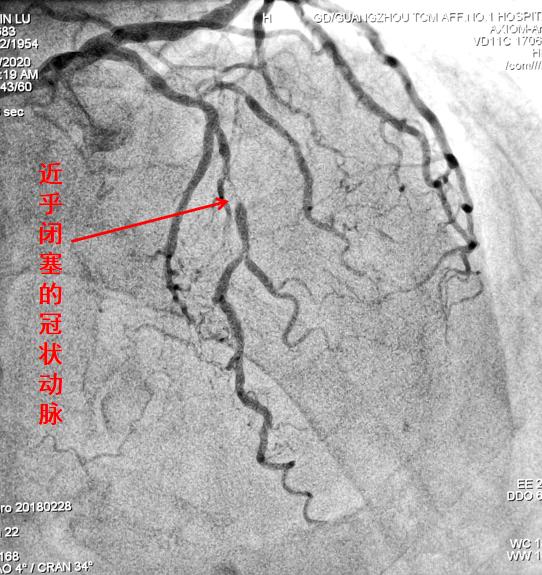

冠状动脉被堵可造成心肌梗死危及生命

动脉被堵而出现缺血,这个好理解。因为动脉不能向器官组织顺利地运送富含氧气和营养物质的动脉血了嘛!器官组织对缺血缺氧常常会以疼痛来作“警示”,比如心脏冠状动脉缺血会出现心绞痛,下肢缺血会出现患肢的剧烈疼痛,肠系膜动脉堵塞也会出现腹痛。随着缺血程度的加重,后续可能引起心肌梗死、肢体冰凉、肠道坏死等严重后果,并均可危及生命。

首先,通过介入血管插管,可以在远离病变、容易操作的部位简便实施。插入的细小导管可顺着血管走行,进行选择性血管造影,从而准确直观地显示出血管堵塞的部位、范围和程度,是诊断血管病变的“金标准”,为下一步的治疗提供有力的依据。

血管造影可清晰显示狭窄闭塞情况,腔内介入快捷有效